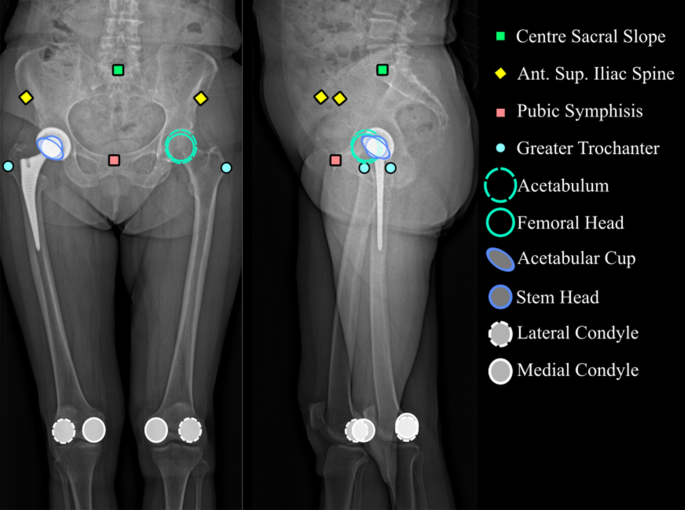

The considered anatomical landmarks (Fig. 2) were the points used to define the geometric model.

Pelvis and femur geometry

The selected 3D geometric parameters of the pelvis and femur were the standard output of sterEOS (Fig. 3). To assess reliability between sessions, parameters that did not depend on posture and that were not affected by surgery were selected (Fig. 4).